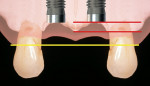

Two Single Impants